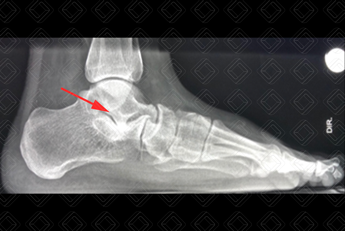

Texto alternativo para a imagem Créditos: Dra. Elazir Mota - Rio de Janeiro/RJ

Descrição da figura: Radiografia de pé direito perfil. O diagnóstico, neste caso, é de coalizão talocalcâneo direito. Há evidente fusão com importante esclerose do tálus e calcâneo direito (seta vermelha).

Coalizão tarsal: Definida por uma fusão anormal entre dois ou mais ossos do tarso e pode ser fibrosa, cartilaginosa ou óssea. Os principais tipos de coalizão são talocalcâneo e calcâneonavicular. As coalizões devem ter seu diagnóstico realizado pois são causa de redução da mobilidade do pé, dor e pé cavo.

Os principais tipos de coalizão são a calcâneo-navicular (45%) e a talo-calcânea.

Diagnósticos diferenciais: O principal diagnóstico diferencial são entre os tipos de coalizão. A coalizão calcâneo-navicular usualmente envolvendo o processo anterior do calcâneo (nariz de tamanduá no estudo em perfil). A coalizão talo-calcânea cursa com sinal do C e bico talar.